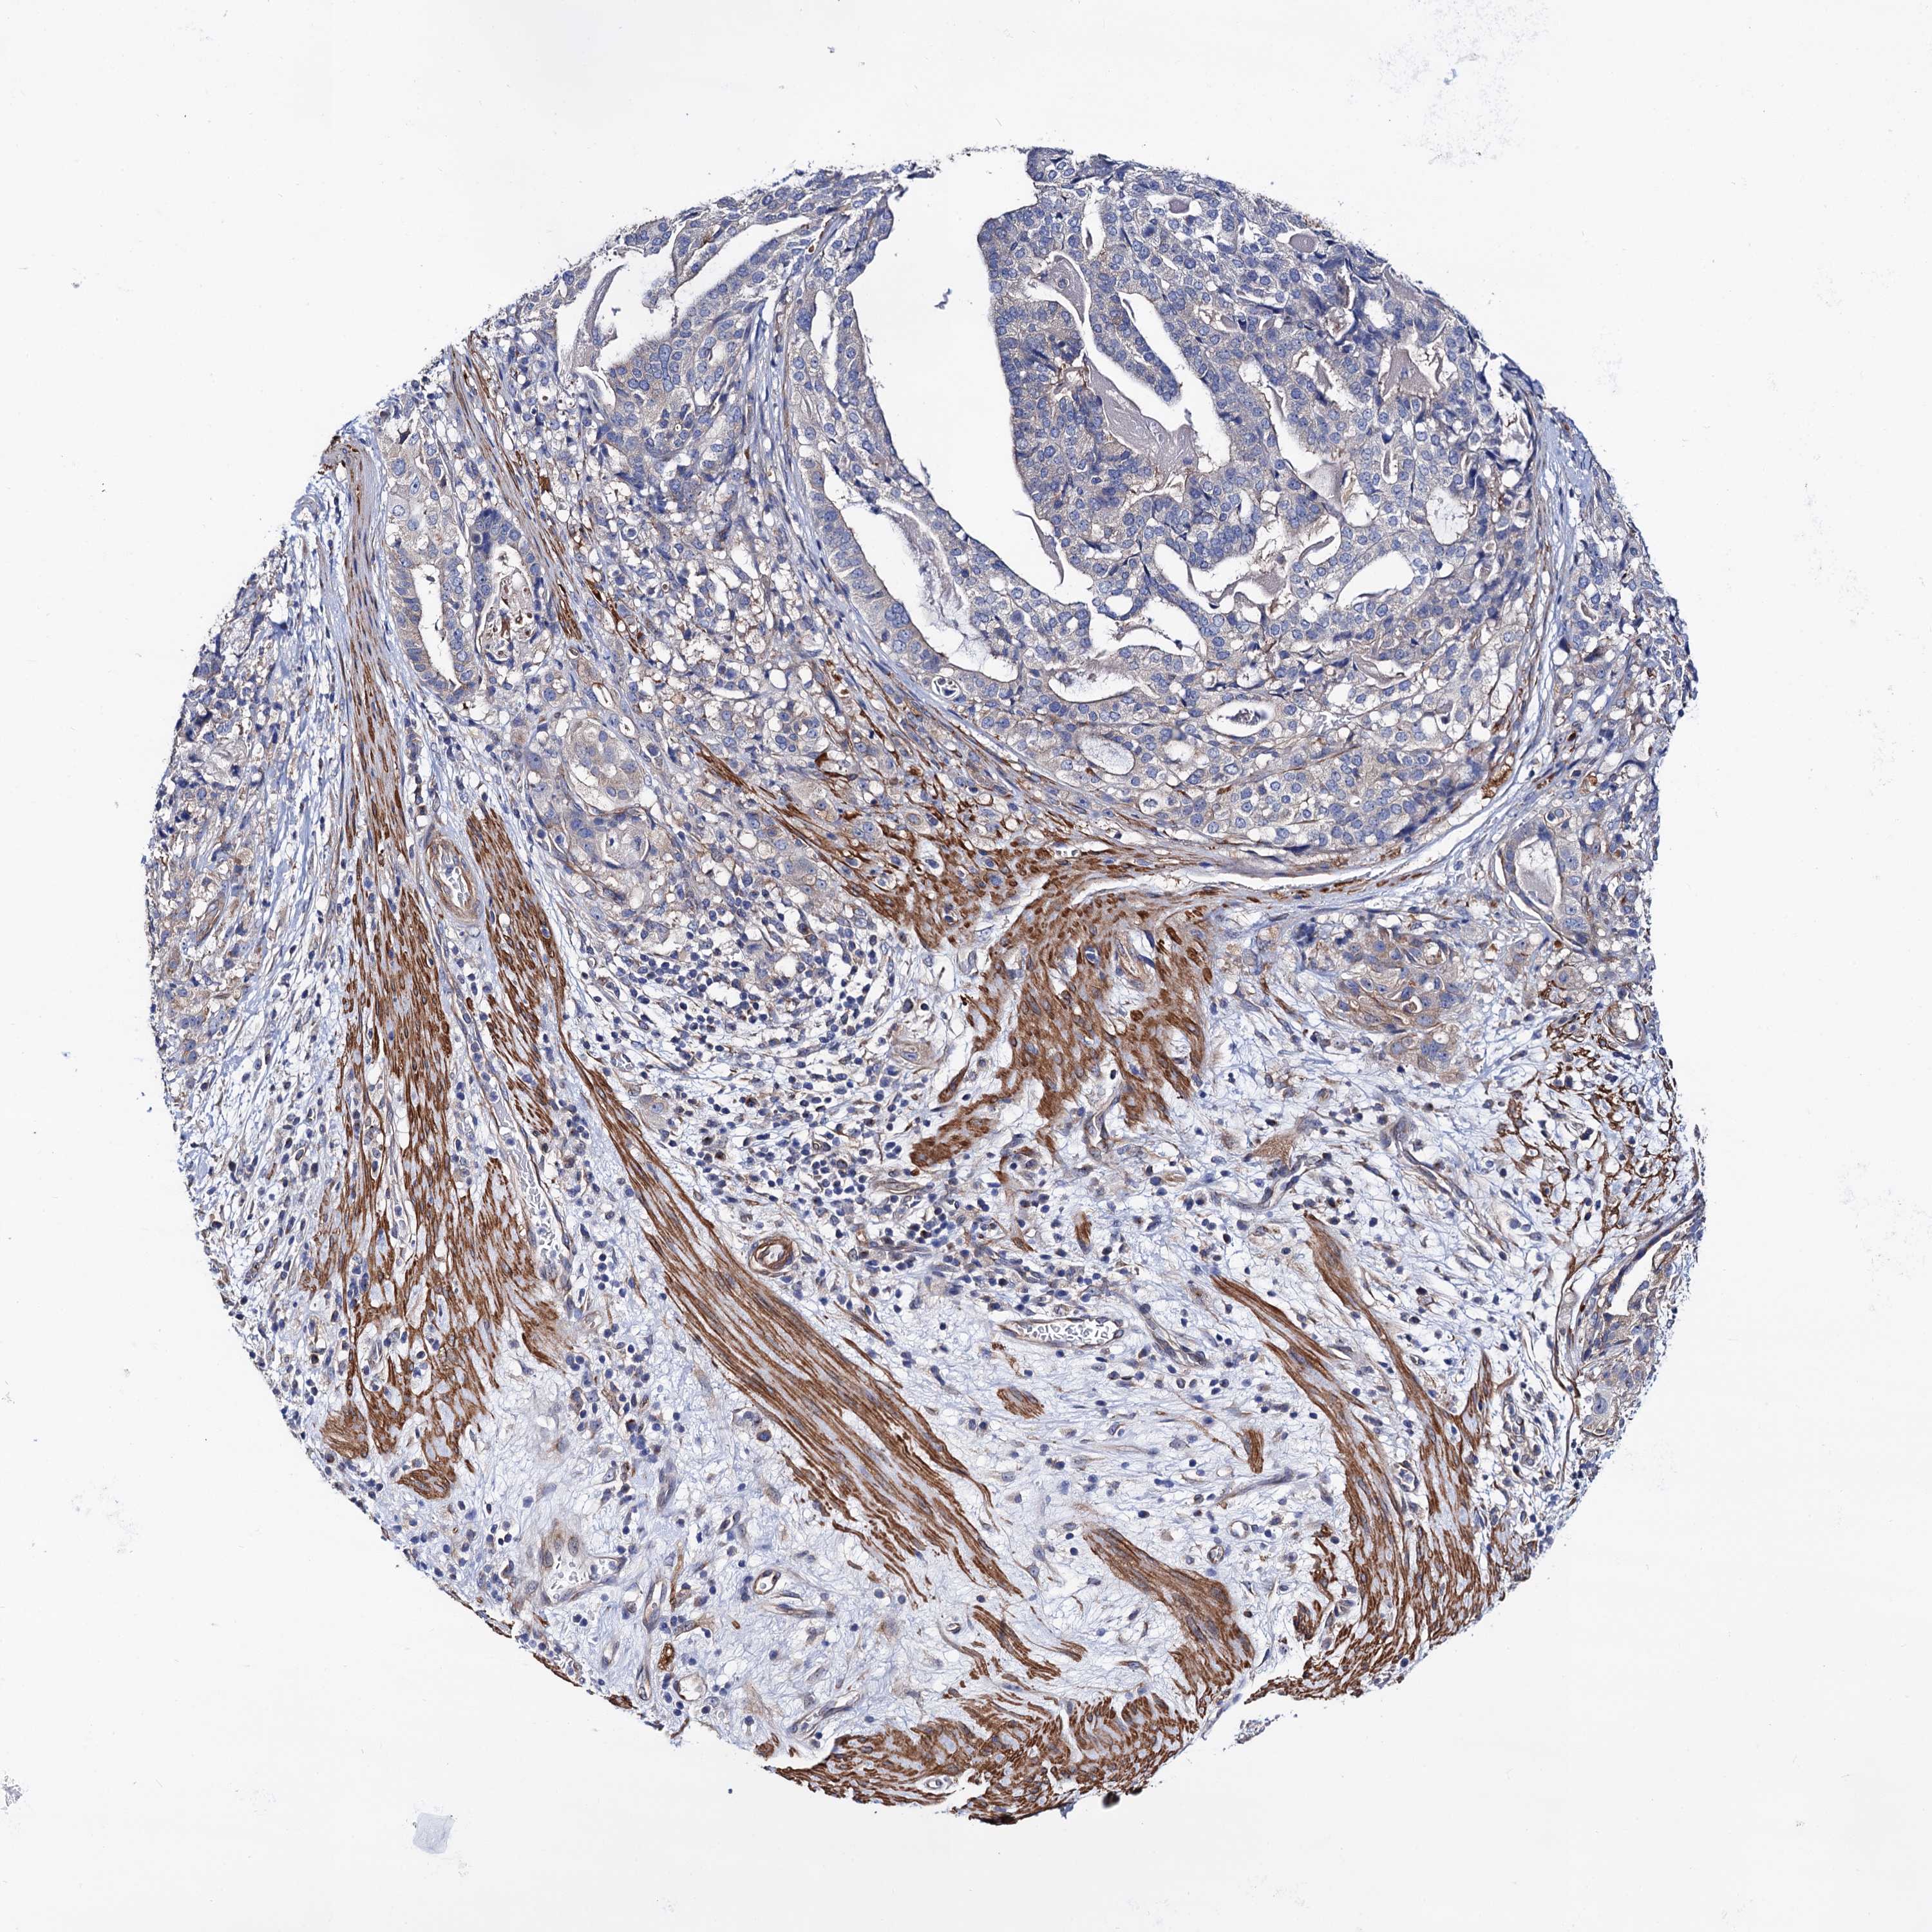

STOMACH CANCER - Protein expressioni

A mouse-over function shows sample information and annotation data. Click on an image to view it in a full screen mode. Samples can be filtered based on level of antibody staining by selecting one or several of the following categories: high, medium, low and not detected. The assay and annotation is described here.

Note that samples used for immunohistochemistry by the Human Protein Atlas do not correspond to samples in the TCGA dataset.

Antibody stainingi

Antibody staining in the annotated cell types in the current human tissue is reported as not detected, low, medium, or high, based on conventional immunohistochemistry profiling in selected tissues. This score is based on the combination of the staining intensity and fraction of stained cells.

Each image is clickable and will lead to virtual microscopy that enables deeper exploration of all samples and also displays staining intensity scores, fraction scores and subcellular localization as well as patient and tissue information for each sample.

Antibody HPA040234

Staining

High

Medium

Low

Not detected

Intensity

Strong

Moderate

Weak

Negative

Quantity

>75%

75%-25%

<25%

None

Location

Nuclear

Cytoplasmic/membranous

Cytoplasmic/membranous,nuclear

Adenocarcinoma, NOS